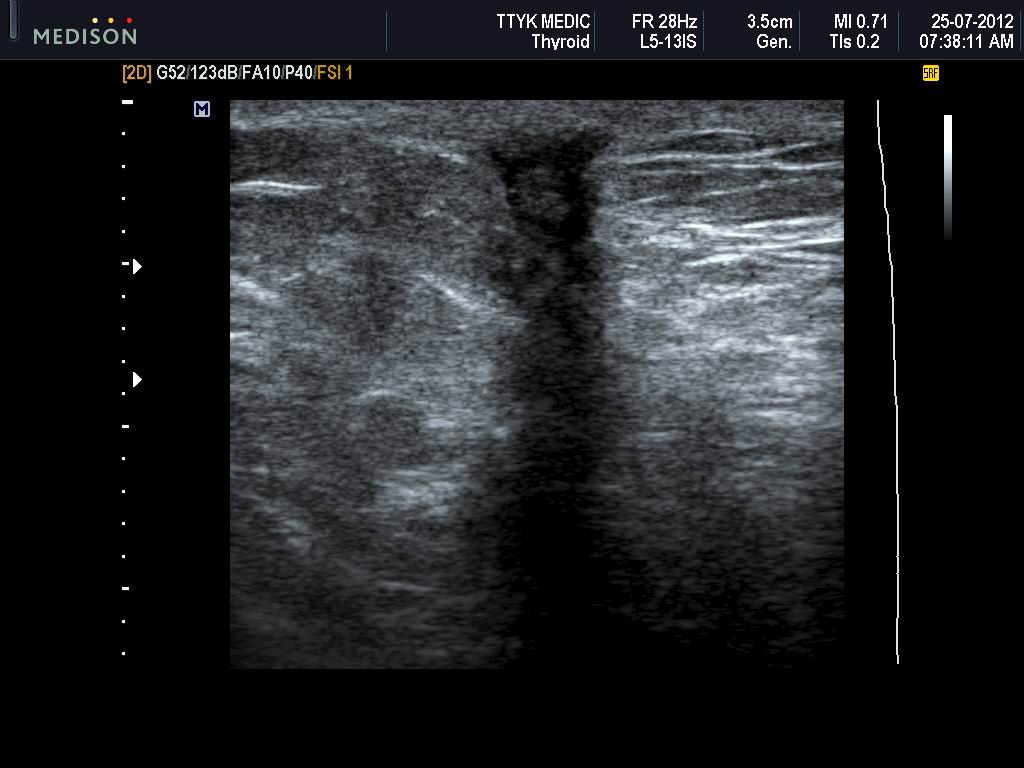

VIETNAMESE MEDIC ULTRASOUND CASE 133 SCAR of REMOVED BREAST TUMOR, Dr Ultrasound Scar Tissue Removal The ultrasound head should be 1.5 or 2 times the size of the treated area. Performed right in our office, the tenex procedure takes less than 30 minutes. Apply a hydrogel sheet over the wound, removing any air bubbles. It is particularly effective for soft tissue injuries and can help decrease. Tenex uses focused aspiration of scar tissue (fast) to. Ultrasound Scar Tissue Removal.